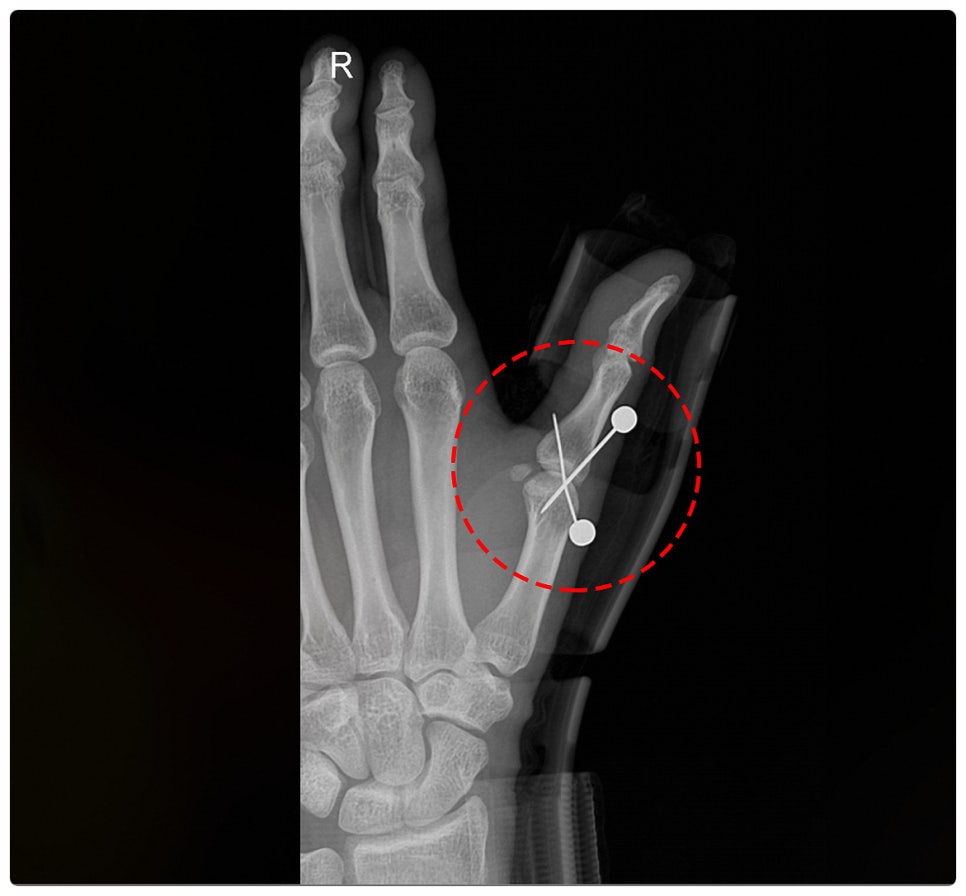

진단명 :

우측 제1수지 근위지골 견열골절 [S62520] 중수지관절 측부인대 파열 [S634-1]

치료 내용 :

관혈적 정복술 및 내고정술, 인대봉합술

견열골절(avulsion fracture)이란 뼈의 일부가 힘줄이나 인대에 의해 강하게 잡아당겨져, 작은 조각으로 떨어져 나가는 골절을 말합니다. 피해자께서도 이러한 견열골절로서, 엄지가 꺾일 때 인대가 뼛조각을 당기면서 같이 떨어져 나간 상태였습니다.

견열 골절의 특징은 관절 근처에서 자주 발생하며, 보통 인대 손상과 동반되는 경우가 많습니다. 그리고 엑스레이 상으로 작은 뼛조각이 떨어져 나간 모습이 확인되며, 향후 운동기능 제한이 생길 가능성이 있습니다.